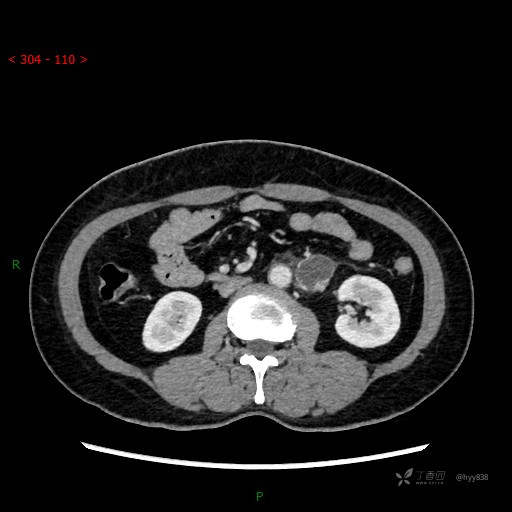

静脉期

CT平扫是外院的,因图像质量原因,不方便上传!